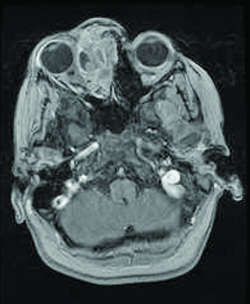

Imaging

On CT scan (Fig. 3 & 4), the tumors appear as homogenous, well-circumscribed, round to ovoid masses, which are isodense to muscle. They are usually within the orbital soft tissues and do not appear to arise from the extraocular muscles. Earlier tumors do not invade bone, however larger tumors are less well defined and may erode bone and extend into the nasopharynx or sinuses. Areas of focal hemorrhage or necrosis may appear heterogeneous on CT scan. Rhabdomyosarcomas demonstrate moderate to marked contrast enhancement.

On MR T1-weighted imaging, the tumor appears hypointense compared with orbital fat, but isointense with respect to extraocular muscles. On T2-weighted imaging, the lesions are hyperintense to orbital fat and extraocular muscles. Areas of chronic hemorrhage may show focal areas of increased signal on T1- and T2-weighted images. They typically demonstrate moderate contrast enhancement with gadolinium injection, particularly with fat suppression.